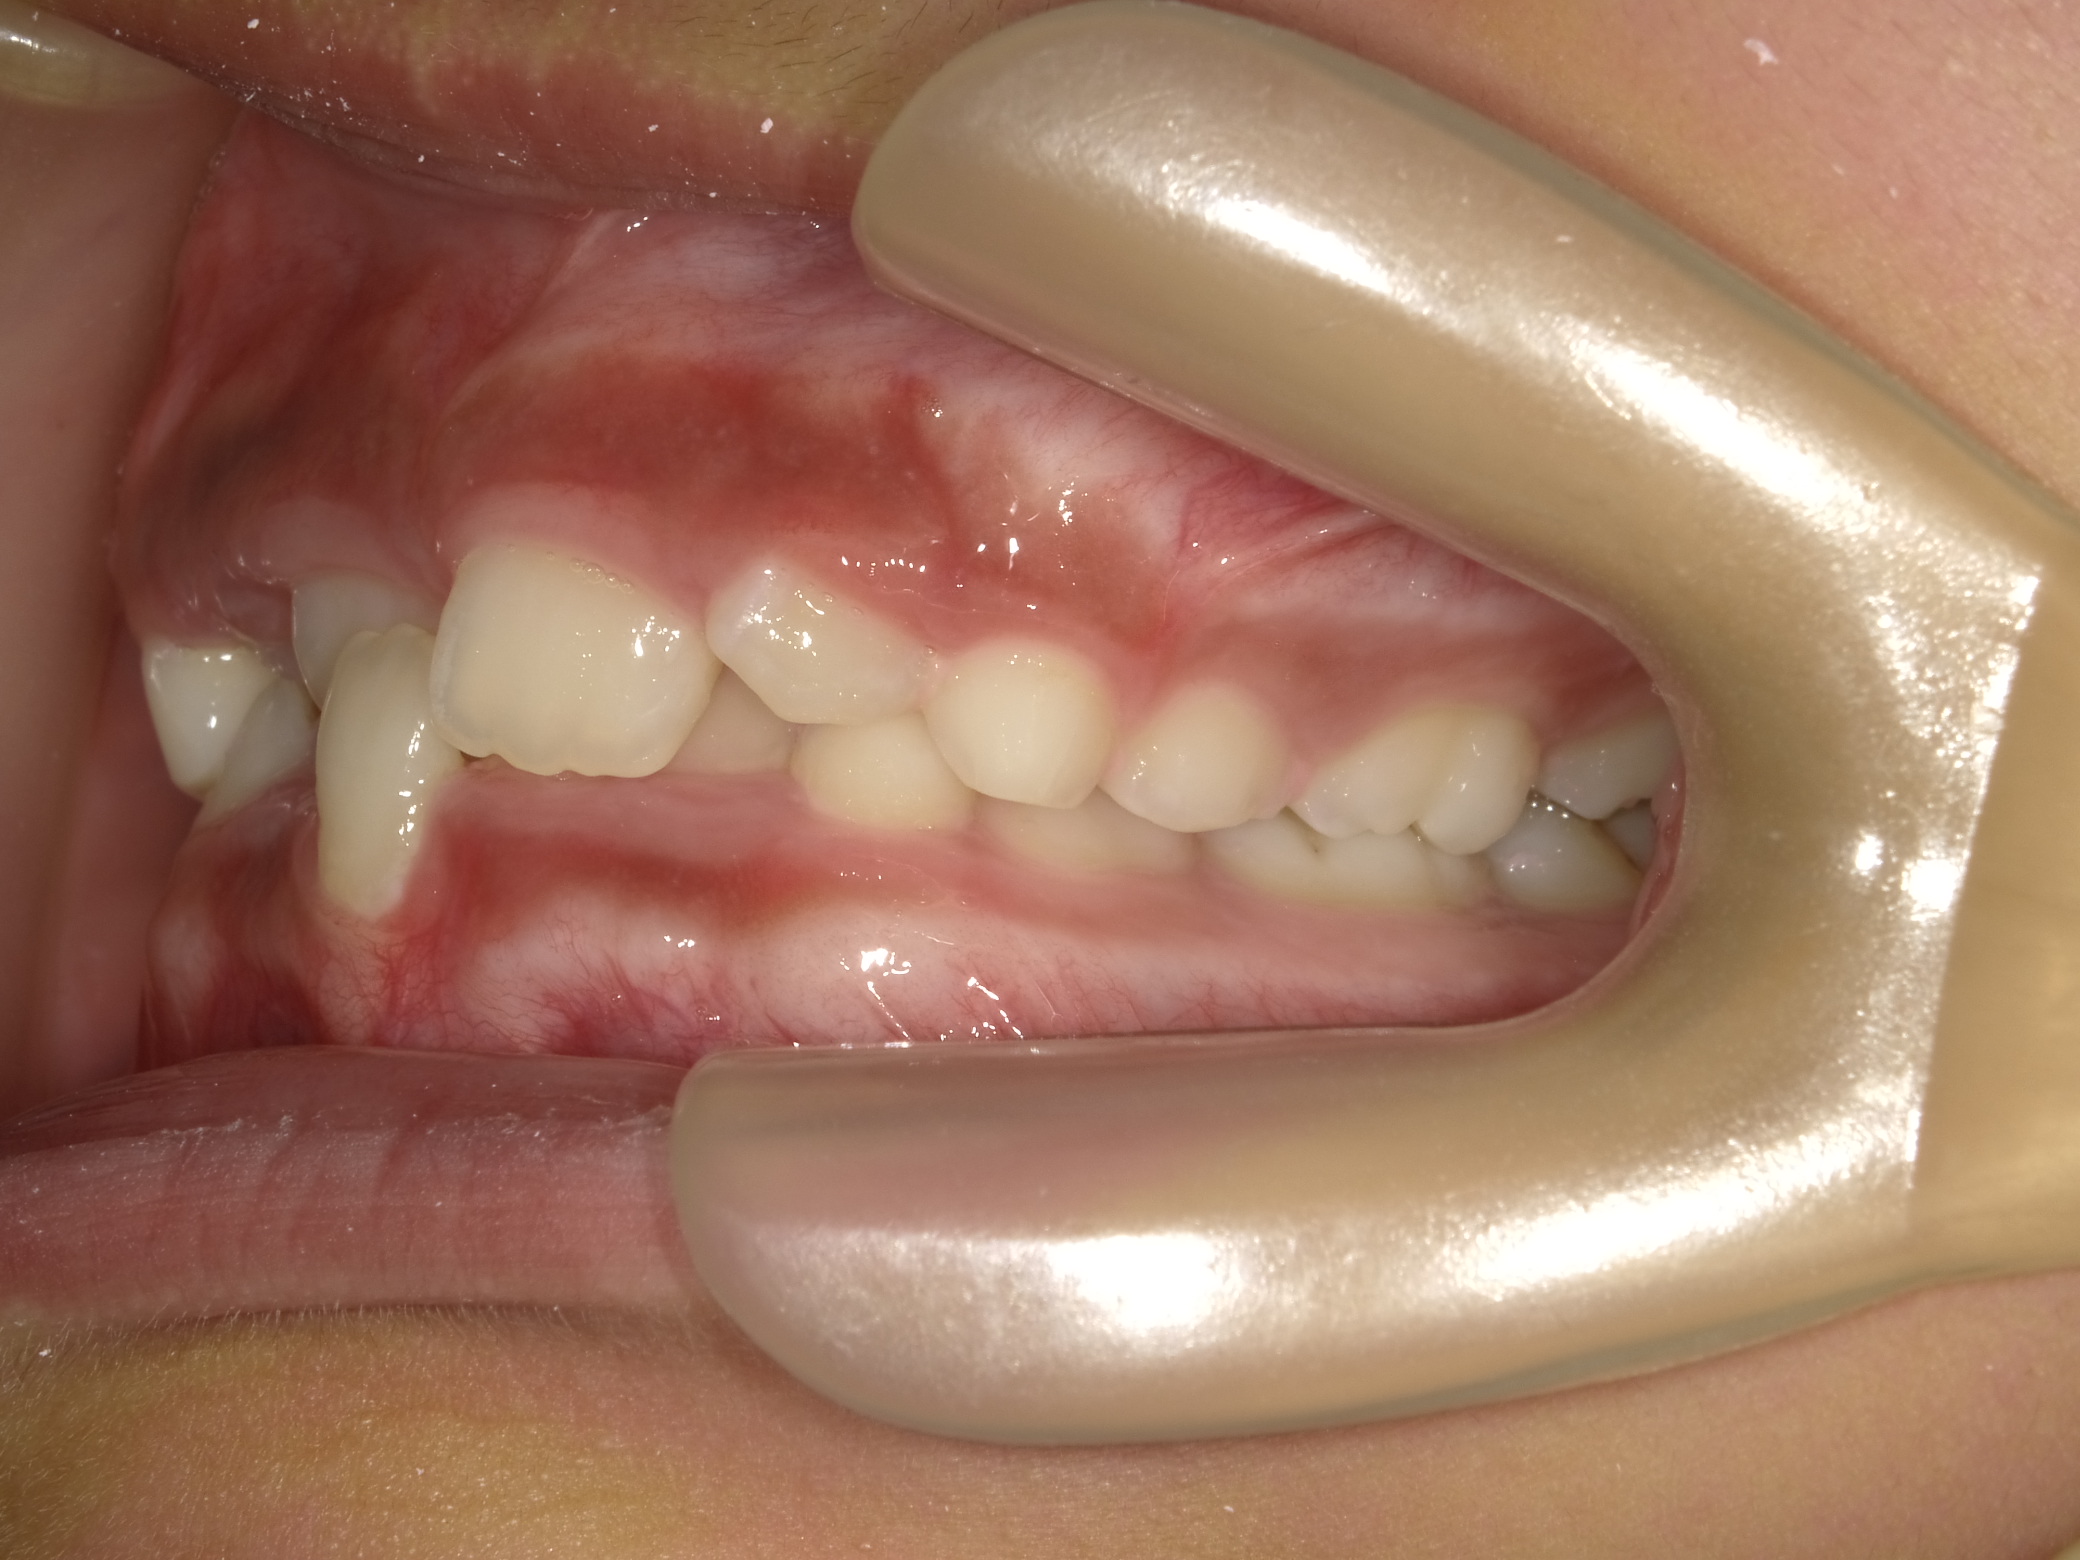

| 症例分類 | 交叉咬合 |

|---|---|

| 主訴 | 前歯がずれて咬んでいる |

| 年齢 | 9歳5ヶ月 |

| 性別 | 女性 |

| 抜歯部位 | なし |

| 使用装置 | 拡大装置、上顎前歯部のセクショナルアーチ装置、取り外し式保定装置 |

| 治療期間 | 1年2ヶ月 |

| 費用 | 相談料0円、検査料50,000円 動的矯正治療費330,000円 調整料6600円×15回分 保定装置料0円 |

| リスク・注意点 | 個々の歯の大きさに対して顎が小さく、歯が並ぶスペースが不足したために交叉咬合が生じています。これらを改善するために、幅の狭搾している歯列を側方に拡大した後、前歯を排列しました。

歯の動き方には個人差があり、予想された治療期間が延長する可能性があります。 治療中は矯正歯科装置が歯の表面に付いており、歯が磨きにくくなるため、むし歯や歯周病が生じるリスクが高まります。ハミガキを適切に行ってお口の中を常に清潔に保ち、さらに、かかりつけ歯科医に定期的に受診することが大切です。 矯正歯科装置の使用状況、定期的な通院など、矯正歯科治療には患者さんの協力が必要であり、それらが治療結果や治療期間に影響します。 治療の経過によっては当初予定していた治療計画を変更する可能性があります。 保定装置の装着時間が十分確保できない場合、歯並びや、咬み合せの「後戻り」が生じる可能性があります。 上下両側第二大臼歯の萌出を観察する必要があります。 |